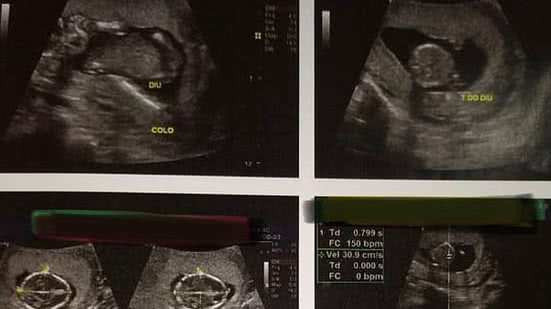

Conselho de Medicina denuncia aborto de paciente que recebeu DIU; Coren contesta

Uma jovem de 23 anos pode ter abortado por conta da implantação do método contraceptivo DIU. O caso aconteceu na cidade de Penedo, e veio a público por meio de nota emitida pelo Conselho de Medicina do Estado de Alagoas (Cremal).

Uma jovem de 23 anos pode ter abortado por conta da implantação do método contraceptivo DIU. O caso aconteceu na cidade de Penedo, e veio a público por meio de nota emitida pelo Conselho de Medicina do Estado de Alagoas (Cremal). O DIU é um dispostitivo implantado justamente para impedir a gravidez e foi implantado na jovem que estaria na 12ª semana de gravidez.

"Sabe-se que a aplicação do DIU está sendo realizada desde o agosto, noa municípios de Penedo e Arapiraca, onde centenas de mulheres já foram submetidas a aplicação. “Para que esse procedimento seja realizado, é no mínimo necessário que se solicite da paciente um teste de gravidez, o beta HCG, e uma ultrassonografia. É uma irresponsabilidade ir adiante com a aplicação do DIU sem ter a certeza que a paciente não está grávida ou com outras enfermidades”, disse Fernadno Pedrosa, presidente do Cremal.